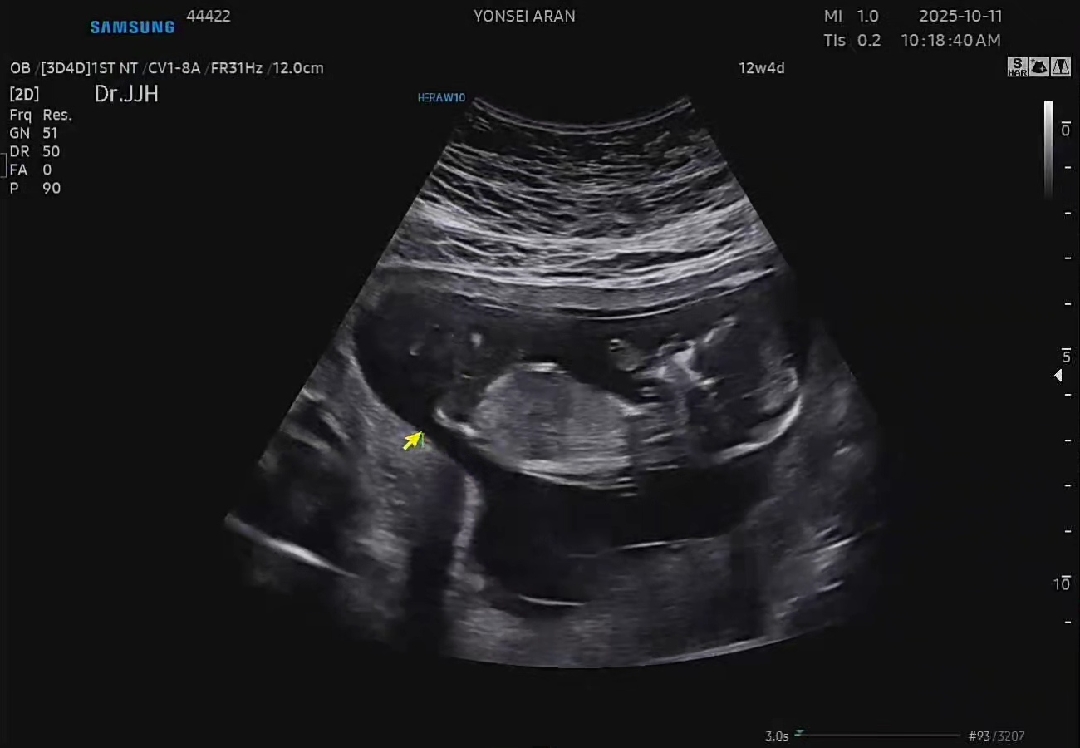

저도 조심스레 각도법 투표부탁드립니다!

12주 4일차입니다! 도당체 어떻게보는지 모르겠어섷ㅎㅎㅎ